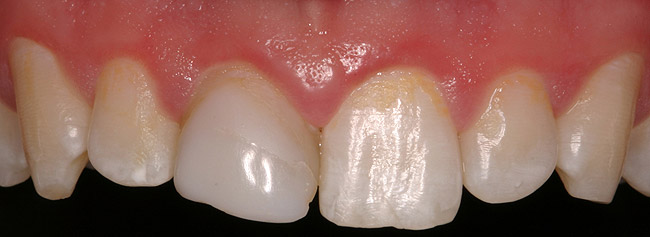

Figure 6a  Upper right central incisor, history of trauma, existing RCT and restoration unsatisfactory.

Figure 6a

Figure 6b  Upper right central incisor, history of trauma, existing RCT and restoration unsatisfactory.

Figure 6b

Figure 6c  Upper right central incisor, history of trauma, existing RCT and restoration unsatisfactory.

Figure 6c